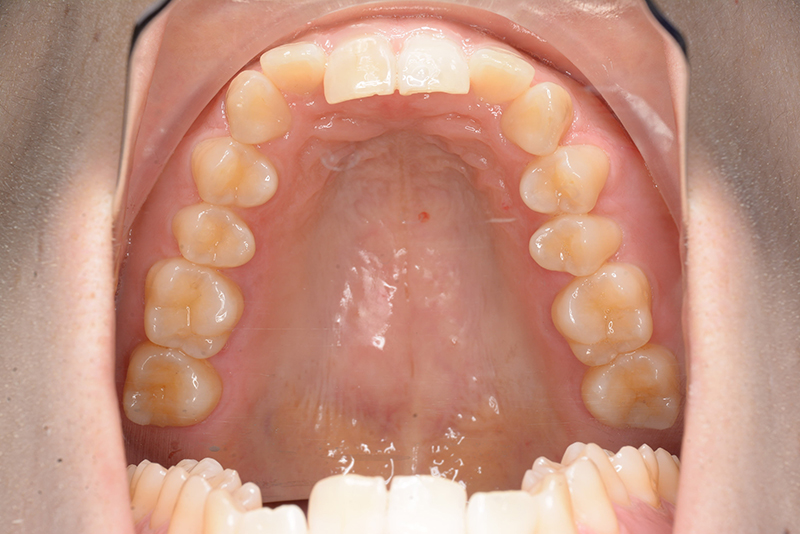

主訴 噛み合わせが深い 診断名 アングルⅡ級2類症例

口腔内所見 大臼歯、犬歯関係はⅡ級で、上顎中切歯は舌側傾斜しており、over jet1.5mm,over bite 6.0mmいわゆるⅡ級2類であった。

批評・予后 上顎臼歯は軽度に近心傾斜しつつ、歯列遠心部には奥行きがあり、下顎歯列には叢生は認められず、スピー湾曲も軽度であること。また軟組織上の問題もないため、上顎歯列の遠心移動による治療が妥当だと判断した。治療後において上顎歯列の遠心傾斜と共に下顎はカウンタークロックワイズローテーションをしながら咬合の緊密化が得られた。